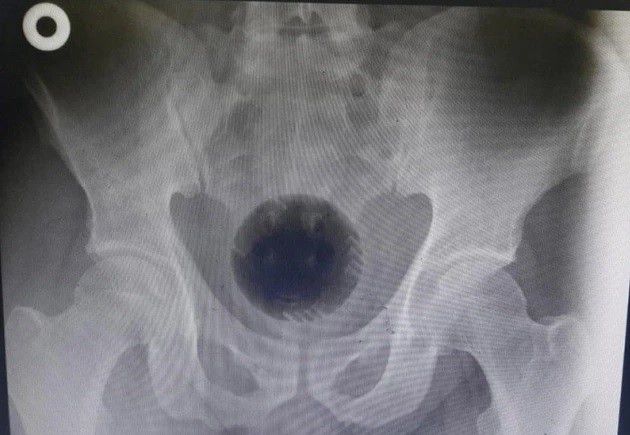

Foto: Hasil CT Scan (Metro.co.uk)

Rupanya dua hari sebelumnya, dia memasukkan bola plastik berdiameter 7 cm sampai 8 cm melalui bokong. Dia beralasan memakai bola tersebut untuk mengobati wasirnya. Padahal saat dilakukan pemeriksaan, dokter tidak menemukan adanya wasir.

Pria itu mengaku sudah berusaha untuk mengeluarkan bola tersebut dengan menggunakan obeng dan sendok. Sayangnya, usaha tersebut tidak membuahkan hasil. Petugas medis lantas memutuskan untuk mengambil tindakan pertama setelah melihat hasil pemeriksaan menggunakan x-ray dan CT scan perut.